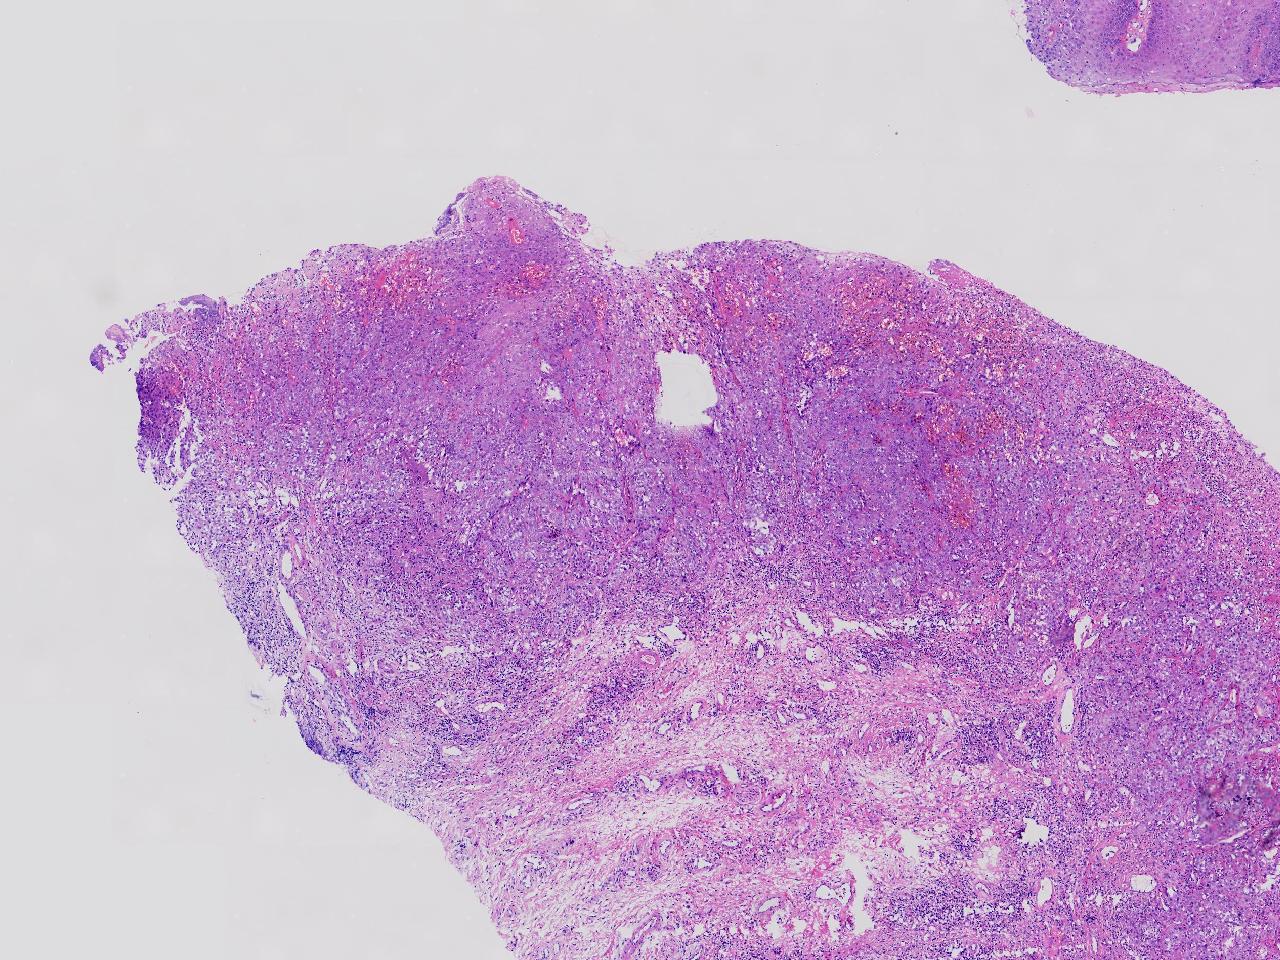

鳞癌?

性别

女

年龄

69岁

临床诊断

外阴肿物性质待查

一般病史

发现外阴肿物1月余,伴外阴疼痛,肿胀色素减退,表面分叶状。

标本名称

外阴肿物

大体所见

灰白色不整形软组织3块。

图3